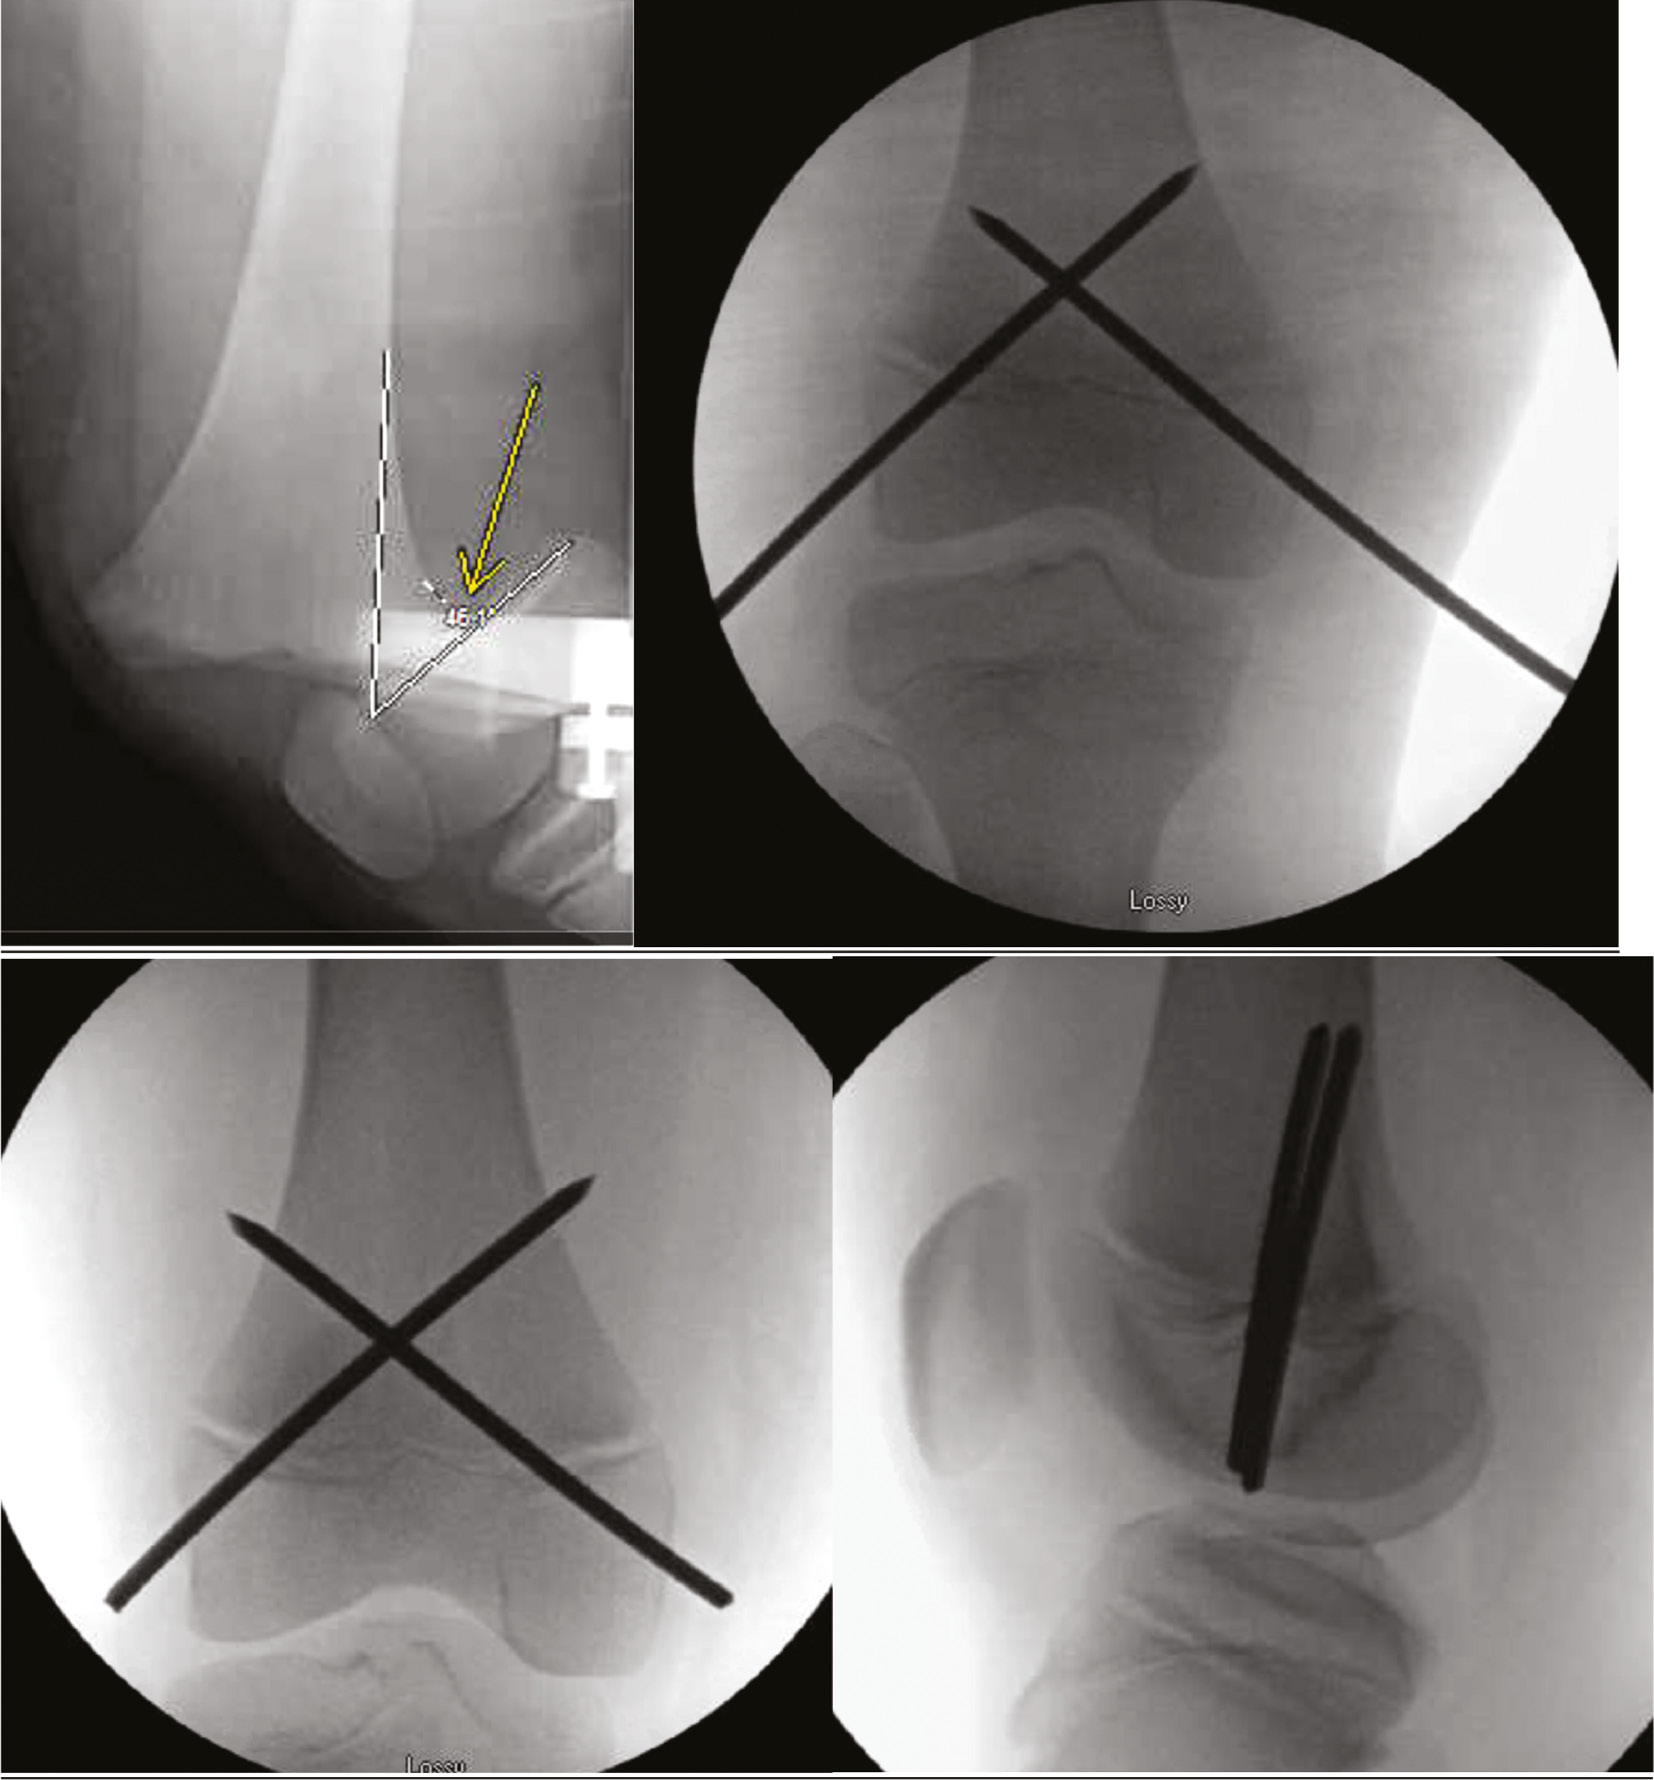

Though some pediatric distal femur fractures are purely metaphyseal, those that involve the physis are associated with a high rate of physeal arrest resulting in limb shortening and angular deformity.56,57 Closed reduction and casting are associated with a high rate of failure.58 Percutaneous pinning is an effective technique for stabilizing these injuries; fortuitously, transphyseal pinning is not independently associated with growth arrest.59

Closed reduction and percutaneous pin fixation can occur in either the supine or the prone position.60 Percutaneous fixation construct consists of two, crossed, transphyseal 3.2-4.5 mm Steinmann pins which may be placed antegrade or retrograde (Figure 15).

Figure 15. A 9-year-old football player sustained a Salter-Harris 1 distal femur fracture. Closed reduction and crossed pin fixation were performed. The pins were likely placed through the joint capsule; thus, to avoid pin tract infection that could lead to septic arthritis, they were cut off below the skin. These pins were removed in the operating room at 5 weeks after injury.